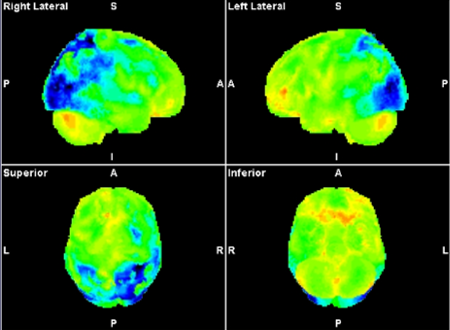

Han beskriver PCA som et syndrom, eller symptomkompleks, som ofte skyldes at man har en Alzheimers sykdom som har begynt på et uvanlig sted i hjernen.

PCA skyldes oftest at Alzheimers sykdom starter på et uvanlig sted i hjernen. Men det kan i sjeldne tilfeller også skyldes andre sykdommer. Det finnes ingen eksakte prosentsatser på hvor mange tilfeller som skyldes andre sykdommer.